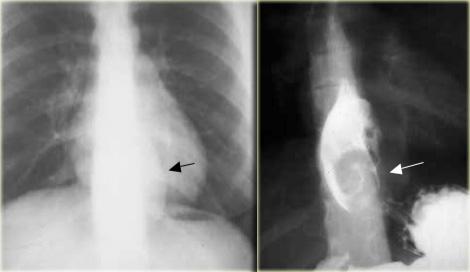

Bên trái là hình ảnh một bệnh nhân bị tụ máu thực quản.

Bệnh nhân nhập viện với triệu chứng đau ngực và khó nuốt sau khi nôn mửa.

Ngoài hình ảnh động mạch chủ ngoằn ngoèo, X-quang ngực bình thường.

Chụp thực quản barium cho thấy lòng thực quản hẹp (các mũi tên) trên phim thẳng và lòng thực quản dẹt trên phim nghiêng (các đầu mũi tên), gợi ý tụ máu trong thành thực quản.

Trên CT, chẩn đoán tụ máu trong thành thực quản được xác nhận.

Khối tụ máu thành thực quản tăng tỷ trọng (đầu mũi tên) được thấy cạnh ống thông mũi – dạ dày (mũi tên).

Sau điều trị bảo tồn, sáu tháng sau chụp thực quản barium cho kết quả bình thường.